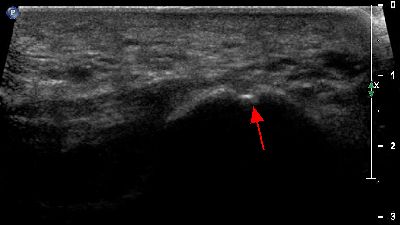

Becco osteofitico falange prossimale becco osteofitico falange prossimale